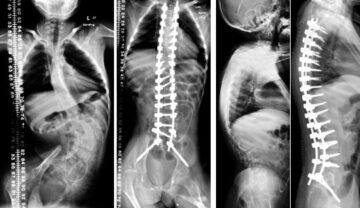

هل تحسّن جراحة اعوجاج العمود الفقري العصبي العضلي جودة الحياة؟ وما النتائج المتوقعة عند الأطفال؟ مقدمة: سؤال مهم يشغل كل أسرة عندما يُشخَّص الطفل بحالة اعوجاج العمود الفقري المرتبط بأمراض عصبية عضلية، يبدأ الأهل

علاج اعوجاج العمود الفقري عند أطفال اعتلال العضلات الخلقي | دليلك لفهم طرق العلاج الحديثة يُعد اعوجاج العمود الفقري (Scoliosis) من المشكلات الشائعة لدى الأطفال المصابين بـ اعتلال العضلات الخلقي (Congenital Myopathy)، وهو أحد

علاج اعوجاج العمود الفقري العصبي العضلي عند الأطفال: دليلك للعلاج ومنع المضاعفات يعاني بعض الأطفال من اعوجاج العمود الفقري المرتبط بأمراض الأعصاب والعضلات، ويُعرف طبيًا بالجنف العصبي العضلي. تظهر هذه الحالة غالبًا عند الأطفال

اعوجاج العمود الفقري العصبي العضلي : الأسباب، الأعراض، وأفضل طرق العلاج يعاني بعض الأطفال والمراهقين من اعوجاج العمود الفقري العصبي العضلي، وهو نوع معقد وخطير من الانحناءات يحدث نتيجة أمراض تصيب الجهاز العصبي أو

أنواع اعوجاج العمود الفقري وأسبابه وطرق العلاج: دليل شامل يُعدّ اعوجاج العمود الفقري (الجنف) من الاضطرابات الشائعة التي قد تصيب الأطفال، المراهقين، أو حتى البالغين. يظهر الجنف على شكل انحراف جانبي غير طبيعي في

الاستعداد لجراحة اعوجاج العمود الفقري العصبي العضلي: خطوات لنجاح العملية وتقليل المضاعفات يُعَدّ اعوجاج العمود الفقري العصبي العضلي من أكثر أنواع الجنف تعقيدًا، حيث يرتبط عادةً بأمراض عصبية أو عضلية تجعل الجسم أضعف وأقل